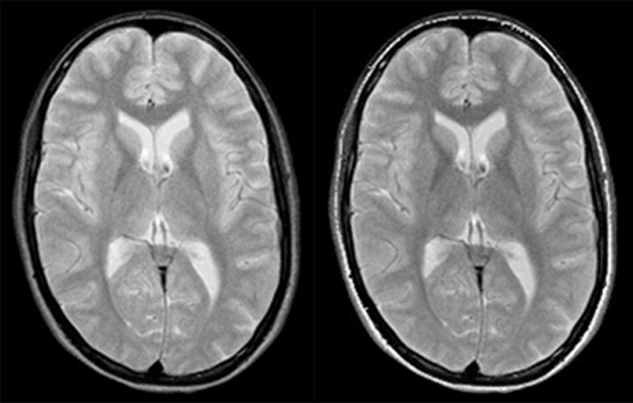

Figure 10-07:

Comparison of rapid spin echo and conventional spin echo.

Left: RSE: ETL = 8; eff. TE = 64 ms; ES = 16 ms; TR = 3000 ms

Right: SE: TE = 64, TR = 3000 ms.

With the exception of the signal from subcutaneous fat, contrast is very similar.

In RSE images, the lipid signal is usually higher than on similar SE images. This is claimed to be caused by several factors, including spin coupling among glyceride protons.

There are also magnetization-transfer phenomena that cause protein containing tissues to appear darker than on similar SE images, whereas hemorrhage with hemosiderin will appear less dark and CSF will appear relatively brighter, obliterating contrast between the ventricles and, e.g., periventricular multiple sclerosis plaques.